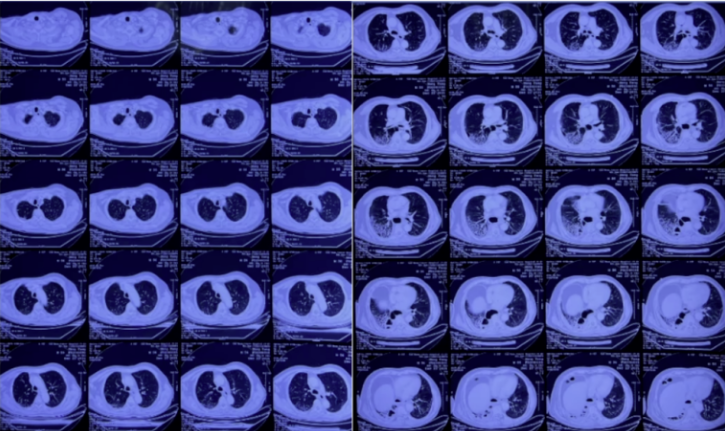

复查胸部CT(2021-12-27):右肺有大片蜂窝状改变,右下肺有脓胸、空洞及纵隔脓肿(图6)。

图6 复查胸部CT(2021-12-27)

思考

患者右肺多发蜂窝状改变的原因是什么?

纵隔脓肿、脓胸的原因有哪些?